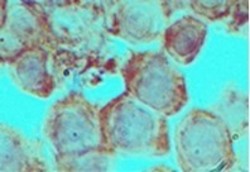

AP21741PU-N IHC

Full details

Method:

Other validation